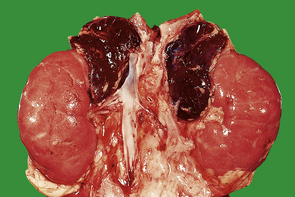

Acute insufficiency

Acute insufficiency (‘adrenal apoplexy’) was first noted in children by Waterhouse and Friderichsen who, in 1911 and 1918 respectively, independently described acute haemorrhagic necrosis of the adrenals in the course of meningococcal septicaemia. Other acute septicaemias, especially those due to Gram-negative bacteria, may cause a similar effect. The adrenal cortices are necrotic and the medullae contain acute haemorrhage (Fig. 17.18). The adrenal necrosis is probably due to disseminated intravascular coagulation (DIC). The symptoms are attributable to lack of mineralocorticoids (salt and water loss with hypovolaemic shock) and of glucocorticoids (failure of gluconeogenesis resulting in hypoglycaemia).

image

Fig. 17.18 Adrenals in Waterhouse–Friderichsen syndrome. The adrenals from a child dying from meningococcal septicaemia are destroyed by haemorrhage.